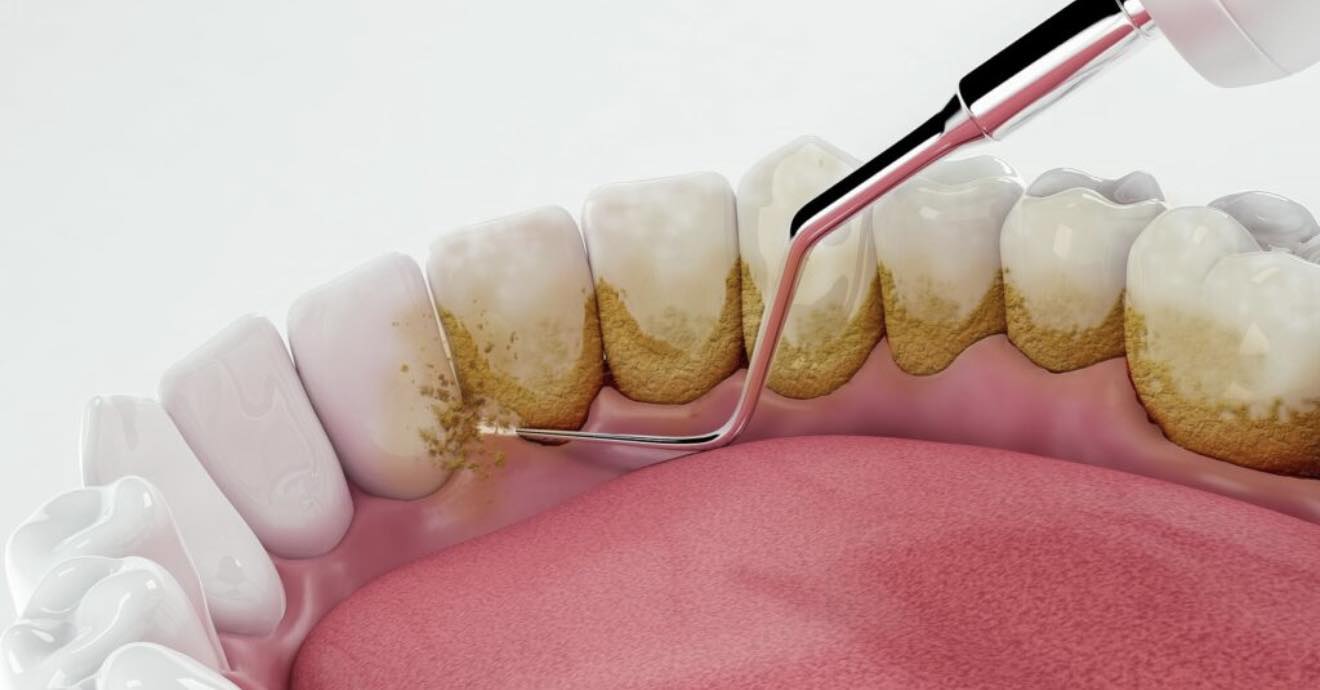

2. რამდენად აუცილებელია პროფესიული წმენდა, თუ სახლში რეგულარულად იხეხავთ კბილებს?

სახლში, იდეალური ჰიგიენის პირობებშიც კი, ნადების დაახლოებით 70-80% სრულად არ იწმინდება, ეს დაგროვილი ნადები კი გარდაიქმნება მაგვარ ქვად, რომლის მოცილება მხოლოდ პროფესიული წმენდით არის შესაძლებელი.

პროფესიონალური წმენდა აუცილებელია ღრძილების ჯანმრთელობის, სუნის პრევენციის და ანთებითი პროცესების თავიდან ასაცილებლად.